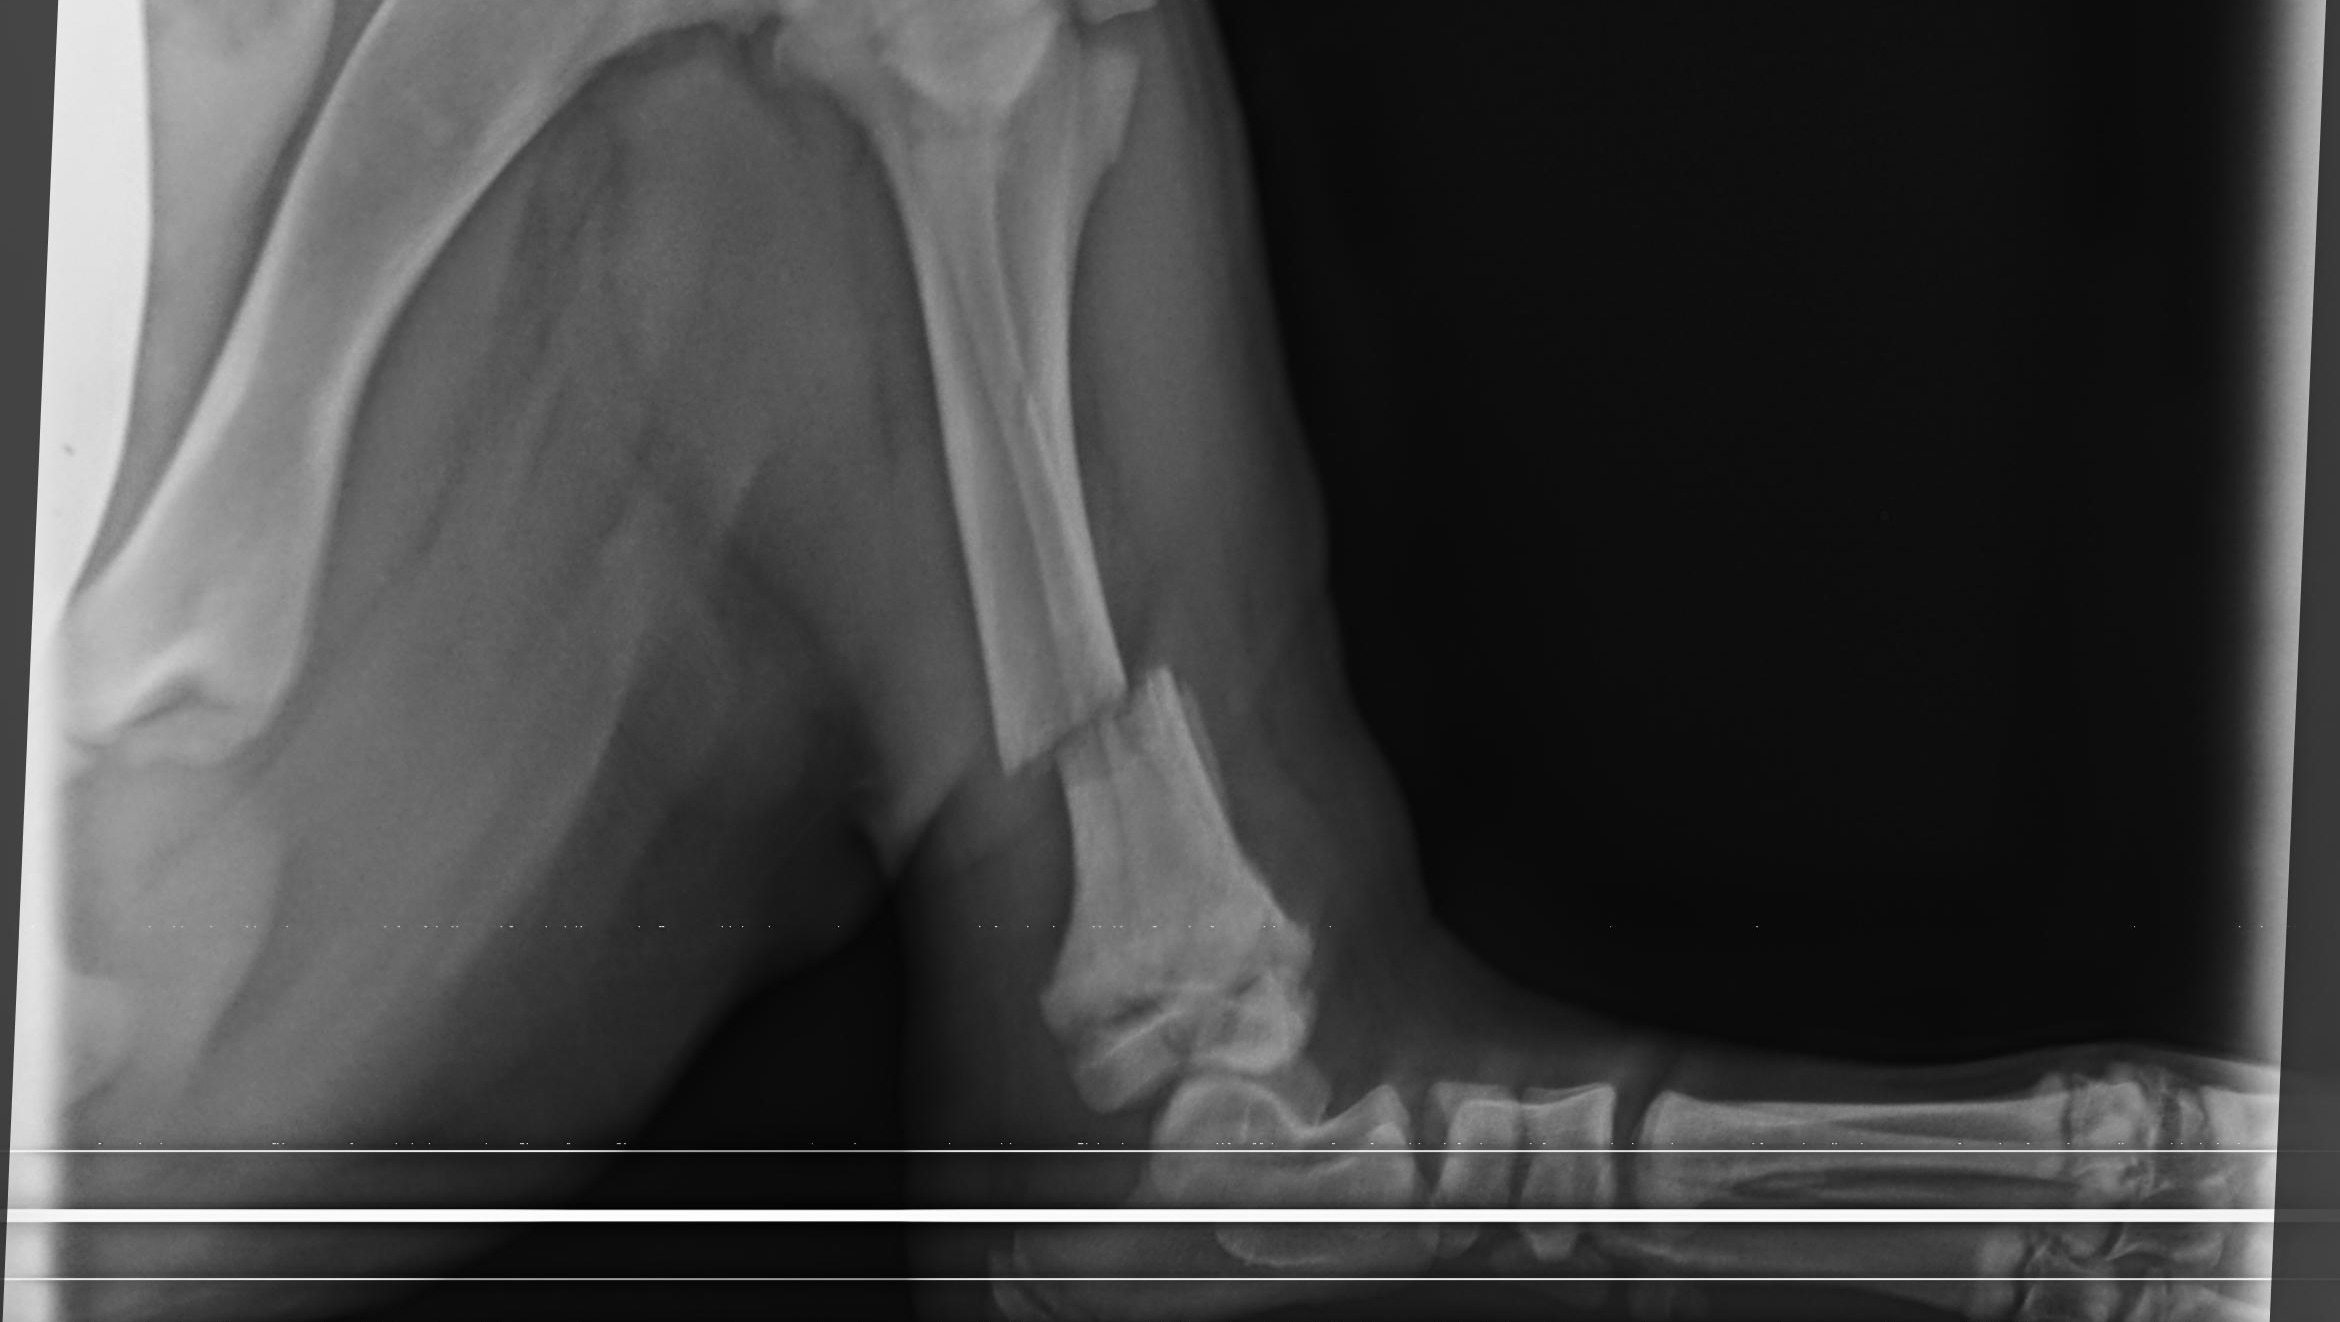

Fuchur wurde auf einer Bergalp in der Ostschweiz geboren. Am 17. September wurde er tragischer Weise von einem Aufbäumenden Rind am linken Hinterlauf Verletzt.

Mit der Besitzerin ging ich noch in der Schweiz am Tag nach dem Vorfall zur Untersuchung/Röntgen zum Tierarzt. Eine

Franktur an der Linke seite Hinten Tibia Fibula war die Diagnose. Da aus Fuchur ein Großer Hund wird, war eine Operation unausweichlich.